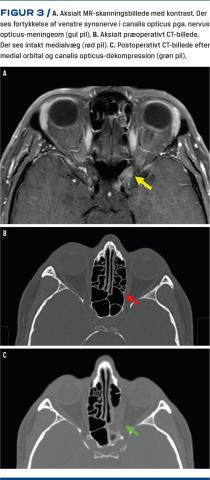

Sygehistorie 2 – dekompression af canalis opticus

En 45-årig mand havde aftagende syn på venstre øje gennem seks måneder. En øjenundersøgelse afslørede venstresidigt papilødem, venøs stase og nedsat visus til 0,5. En computerperimetriundersøgelse viste synsfeltspåvirkning i de temporale kvadranter. Der blev foranlediget en MR-skanning, som viste en fortykkelse af venstre synsnerve (Figur 3), hvilket var radiologisk foreneligt med et nervus opticus-meningeom beliggende i canalis opticus. Pga. det formodede meningeoms lokalisation vurderedes det ikke at være muligt at fjerne selve meningeomet operativt. Da patienten havde et hastigt progredierende synstab, fandt man derimod indikation for ossøs dekompression af nerven ved en endoskopisk endonasal åbning af canalis opticus (Figur 3). Dagen efter dette indgreb kunne han udskrives til eget hjem. Umiddelbart postoperativt bemærkede han subjektiv synsbedring. Ca. en måned postoperativt havde han fortsat subjektiv bedring af synet. Dette blev bekræftet ved en oftalmologisk objektiv undersøgelse, hvor visus på venstre side var fuldt normaliseret fra oprindelige 0,5 til 1,0. Desuden var synsfeltsdefekten aftagende med mean deviation fra –4,45 dB til –3,4 dB. Han blev efterfølgende fulgt med regelmæssige skanninger og øjenundersøgelser.